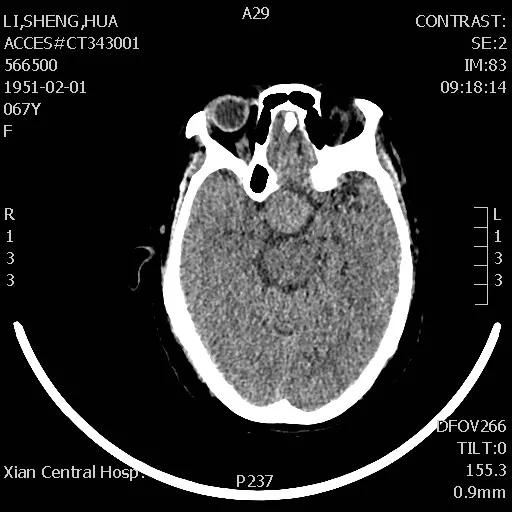

手术于次日下午进行,整个过程非常顺利,患者预后也非常理想,术后复查CT显示肿瘤切除干净,患者视力改善明显,经过一段时间的后续治疗,患者已痊愈出院。